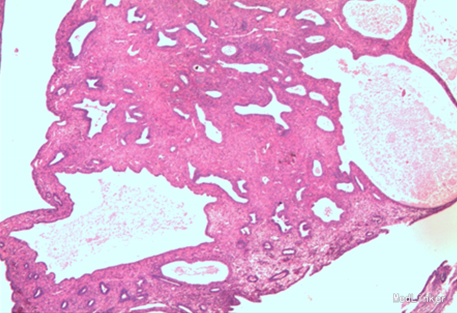

诊断:子宫脱垂III度、阴道前壁中度膨出、阴道后壁轻度膨出 手术方式:阴式全子宫切除术+阴道前后壁修补术